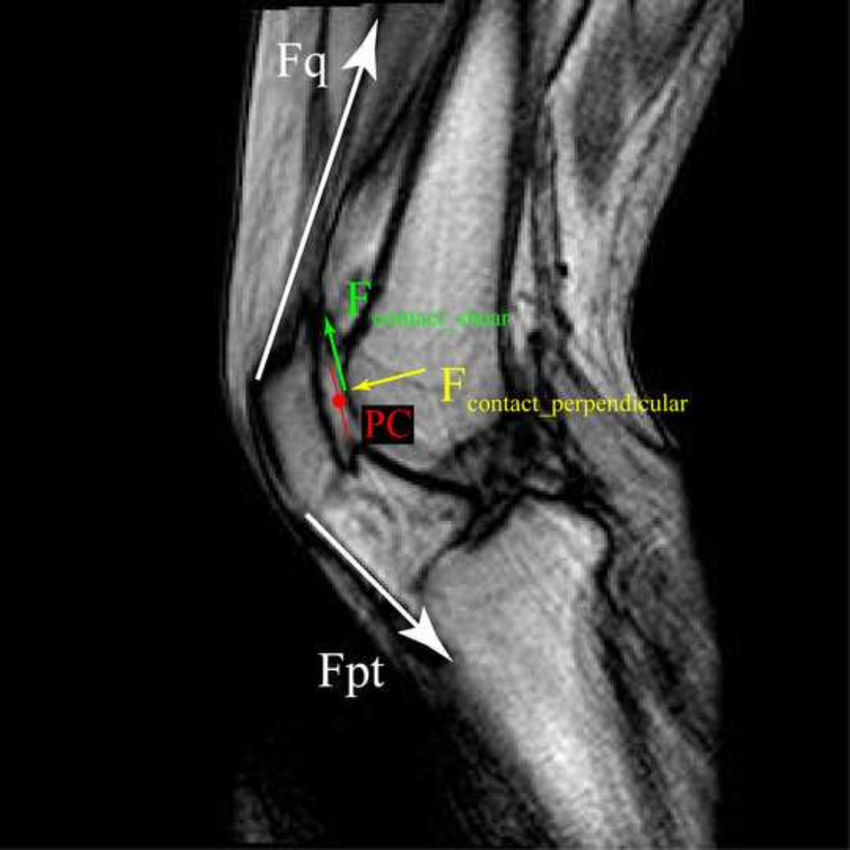

Kolennní klouby slouží v lidském těle především k přenosu dynamiky přirozeného pohybu směrem vpřed, tedy k bezproblémové chůzi. To znamená k využití setrvačnosti vzniklé z podvolení se trupu (páteře) zemské gravitaci v nepřetržitém volném pádu, kterým lidská chůze v podstatě je. Tento efekt dovoluje člověku snadno překonávat libovolné vzdálenosti...